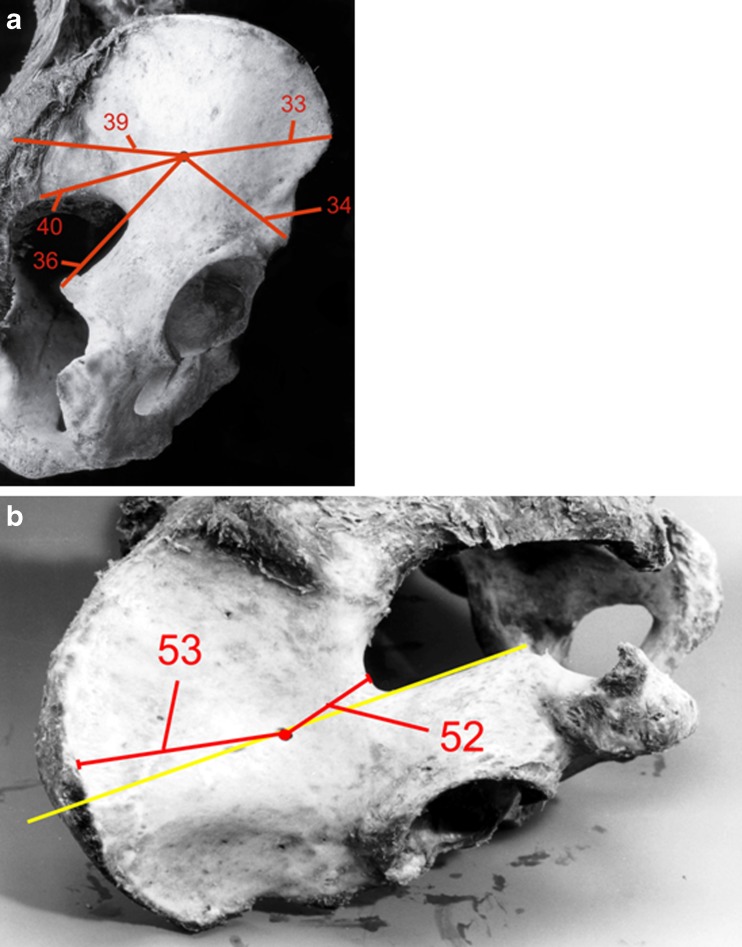

Fig. 3.

a, b Specimen with antegrade entry point of anterior column screw. Distances to the different bony landmarks are marked in straight lines. Numbers are for identification use

When placing the anterior column screw in the antegrade direction (Table 2), the distance to the anterior inferior iliac spine was significantly different between sexes (p = 0.007). The distance to the posterior superior and inferior iliac spine was the most consistent distance between sexes, with differences in mean values <0.5 cm.

Table 2.

Distance of screw entry point to various landmarks. Identification number in brackets (see Fig. 3a,b)

| Distance of antergrade entry point anterior column screw to various landmarks | Male specimen | Female specimen | P value |

|---|---|---|---|

| Mean [cm; (range) standard deviation] | |||

| Anterior superior iliac spine (33)a | 7.1 (6.2–8.0) 0.61 | 6.6 (5.5–7.7) 0.86 | 0.224 |

| Anterior inferior iliac spine (34)a | 6.5 (5.0–8.5) 1.23 | 4.7 (4.0–5.3) 0.46 | 0.007 |

| Iliac crest (36)a | 9.3 (8.5–10.7) 0.76 | 7.8 (6.0–9.0) 1.21 | 0.025 |

| Posterior superior iliac spine (39)a | 10.3 (8.4–11.6) 1.38 | 10.5 (9.5–12.0) 0.86 | 0.949 |

| Posterior inferior iliac spine (40)a | 7.4 (6.6–8.9) 0.93 | 7.3 (5.8–8.5) 0.96 | 0.949 |

| Vertex of greater sciatic notch (52)a | 4.2 (3.4–5.4) 0.70 | 3.7 (2.5–4.9) 0.96 | 0.276 |

| External lip of iliac crest (53)a | 6.6 (5.0–7.9) 1.09 | 6.9 (5.8–7.7) 0.67 | 0.607 |

asee Fig. 3a, b